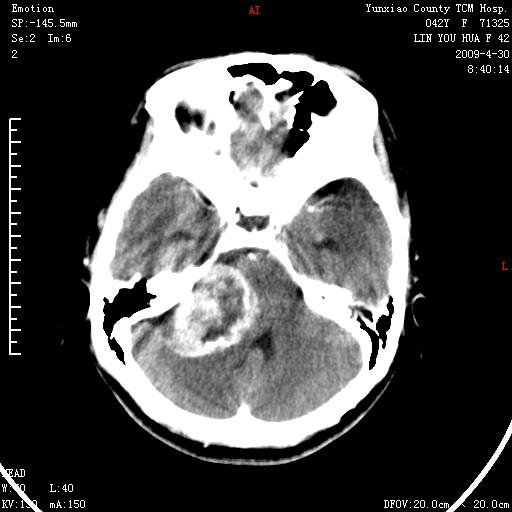

右侧桥小脑角区肿瘤,高密度囊变有显著强化,骨窗见内听道显著扩大,考虑听神经瘤可能性大

1)右侧听神经瘤。2)阻塞性脑积水。